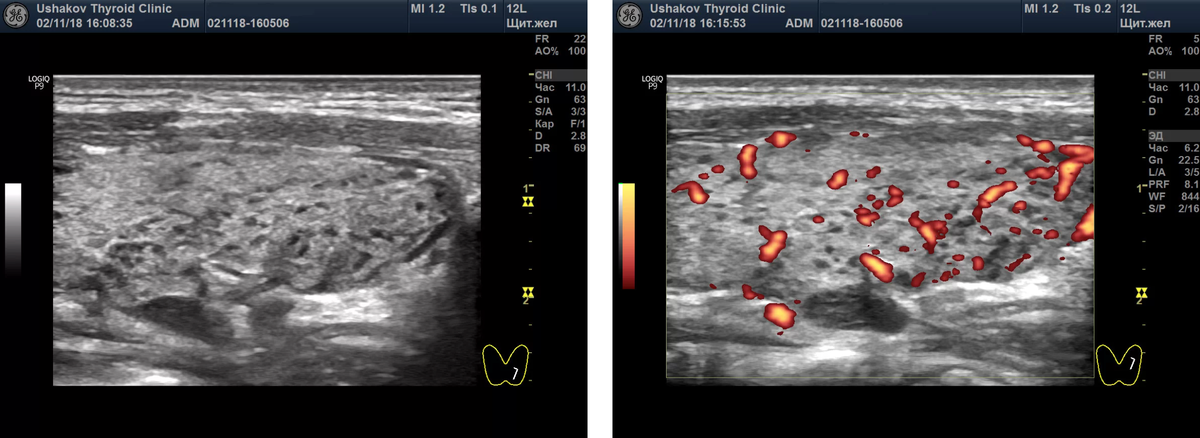

Слева снимок показывает: в доле щитовидной железы виден крупный сегмент, в котором множество долек содержат темную (гипоэхогеную) ткань - признак разрушения ткани ЩЖ и присутствия иммунных клеток лимфоцитов. Интенсивность кровотока в этом сегменте доли увеличена до умеренной степени (снимок справа). Из монографии А.В. Ушакова.

4. Интенсивность кровотока.

Это самый показательный и лабильный показатель напряжения (в том числе перенапряжения) щитовидной железы. И уже несколько раз рассказывал и показывал в статьях, фильмах и монографиях принципы и методику диагностики величины напряжения (и ПЕРЕНАПРЯЖЕНИЯ) ткани щитовидной железы по интенсивности кровотока и скорости кровотока в сосудах.